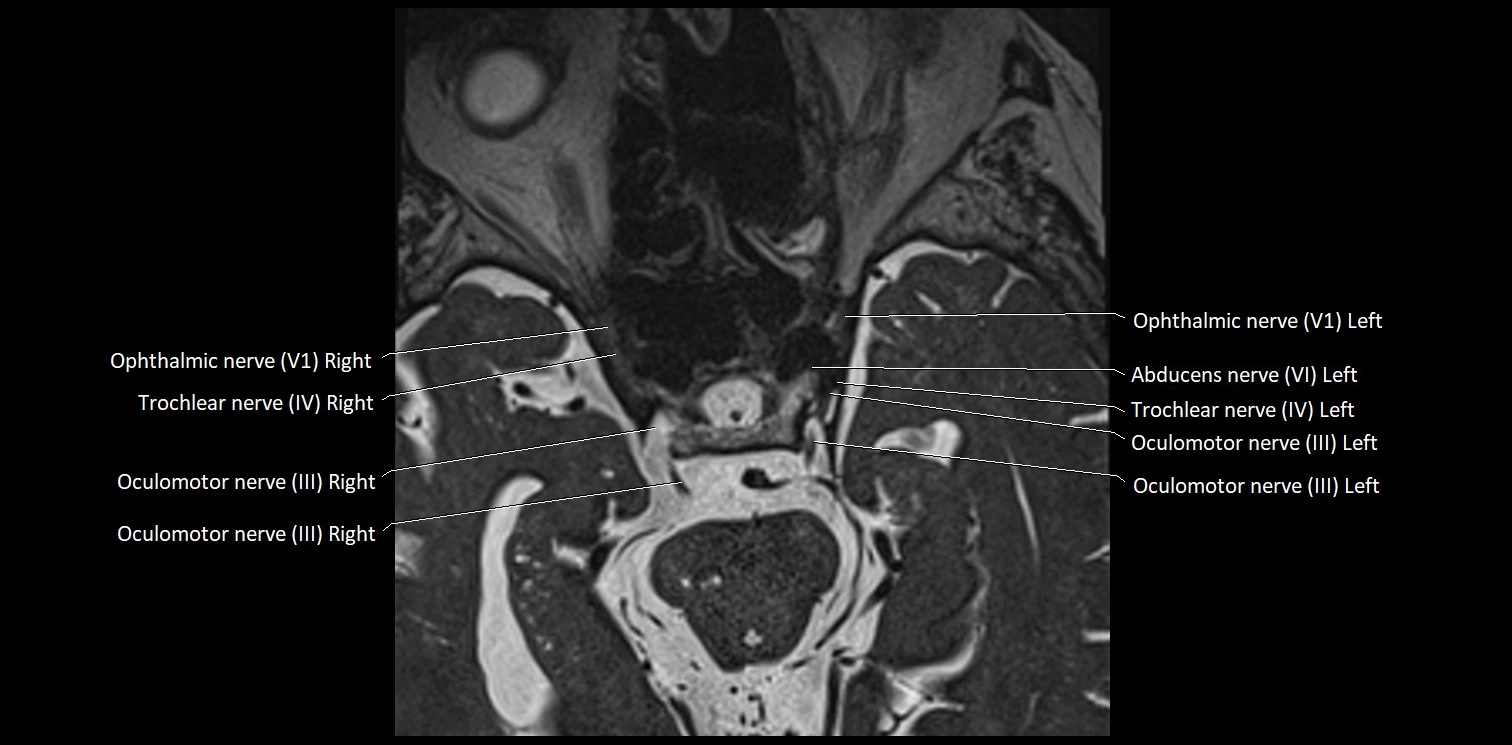

MRI Appearance

• The abducens nerve is a small, thin, linear structure

• Best visualized on high-resolution T2-weighted 3D MRI sequences (e.g., FIESTA or CISS)

• Seen as a hypointense (dark) line running from the brainstem at the pontomedullary junction, traversing the prepontine cistern, and entering Dorello’s canal under the petrosphenoidal ligament, then into the cavernous sinus, and finally the orbit

• May be challenging to visualize in standard MRI due to its small size

• Pathology may be inferred by absence, displacement, or enhancement of the nerve

MRI images

image